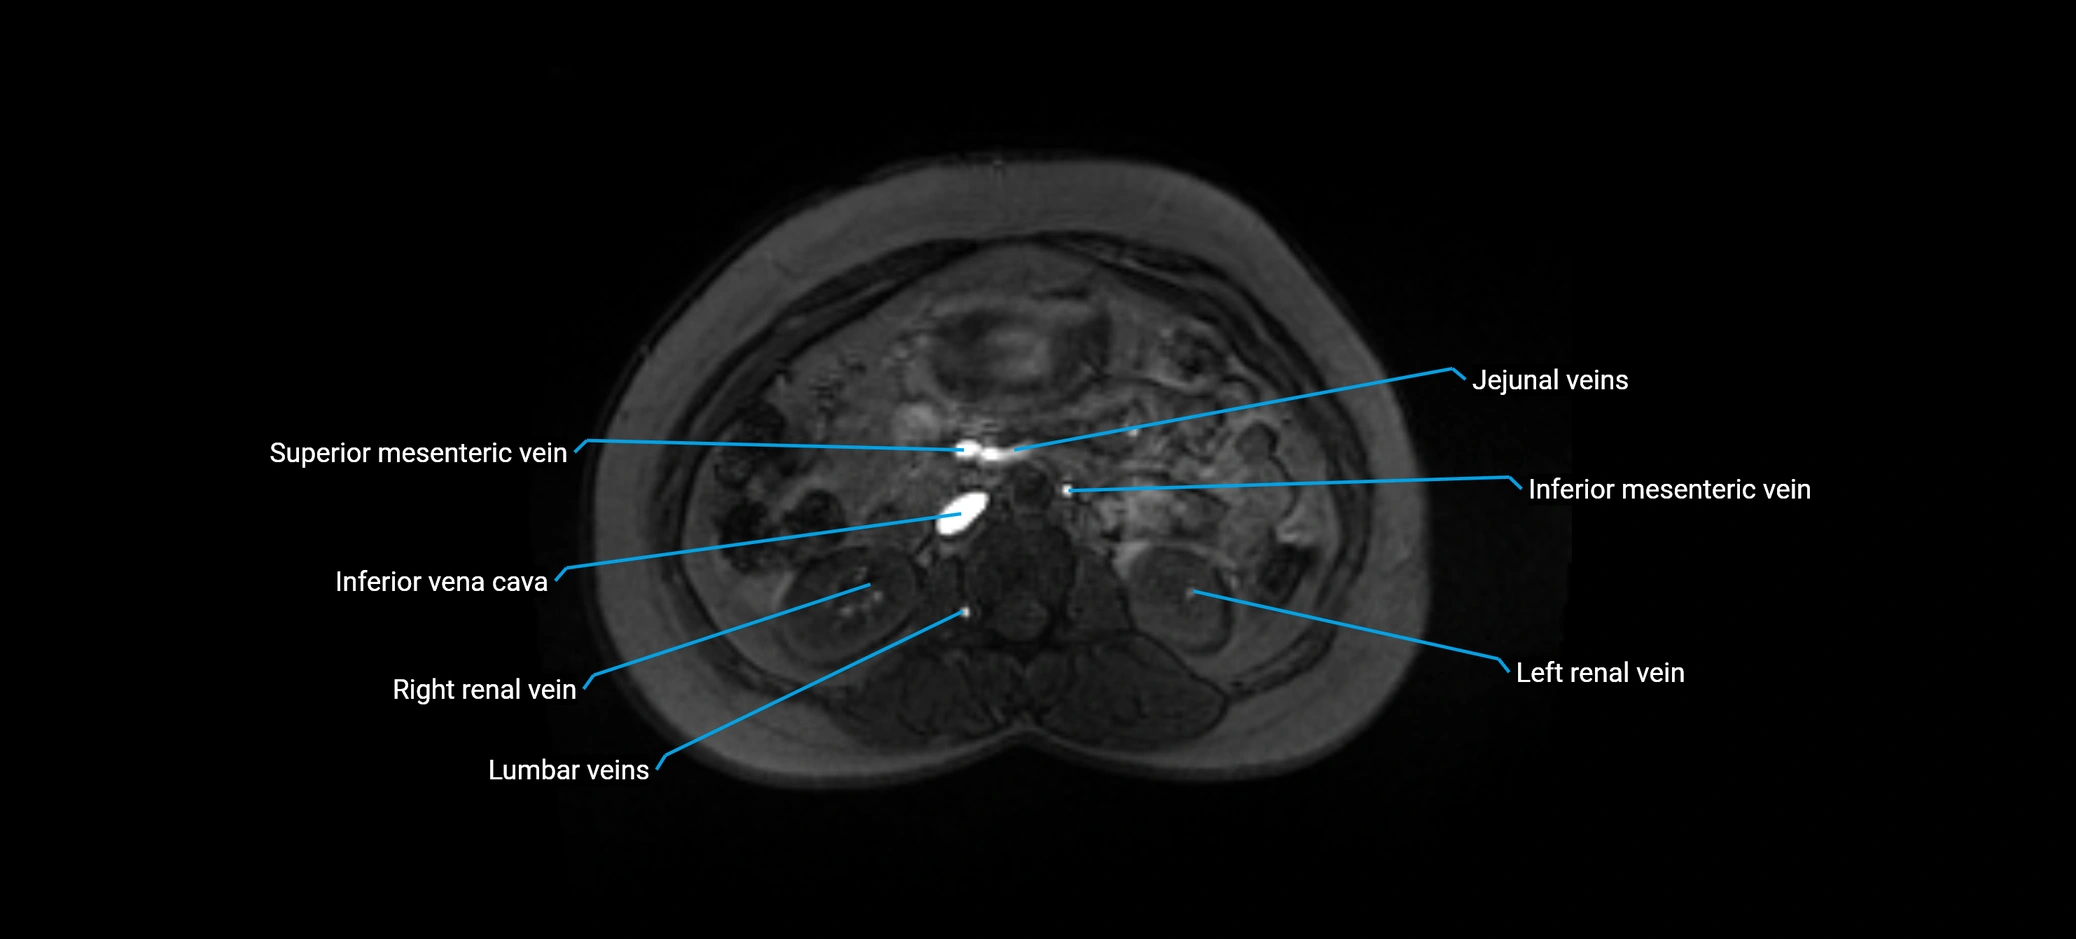

MRI image

image